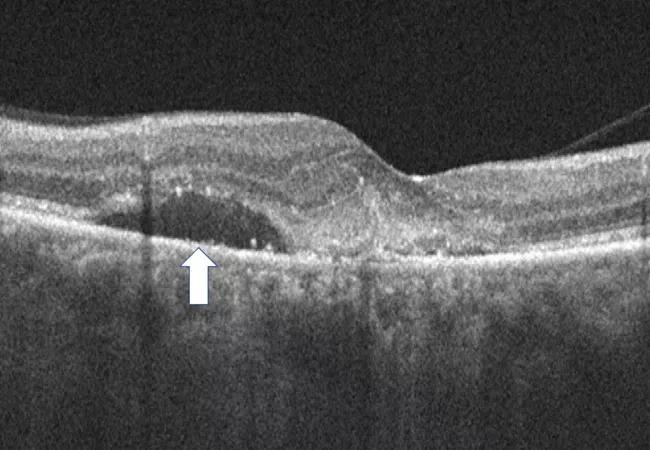

The impact of subretinal fluid on overall outcomes in neovascular AMD (nAMD) has been controversial. Multiple studies have demonstrated that the very presence of subretinal fluid may not have a negative impact on overall visual acuity. In some cases it may be associated with better overall visual acuity. However, recent studies have shown that overall fluctuation in retinal thickness may have negative implications. This generates new and important questions related to the specific types of fluid that are causing the fluctuations in retinal thickness and their impact on anatomy and visual outcomes.

In a recent post hoc analysis of the OSPREY study, led by Justis P. Ehlers, MD, of Cleveland Clinic Cole Eye Institute, subretinal fluid stability (i.e., lack of fluctuation whether fluid is absent or present) in nAMD appears to be associated with better overall anatomic and functional response to anti-vascular endothelial growth factor (VEGF) therapy. Greater fluid volatility may signal the need for more aggressive treatment due to risk for progressive ellipsoid zone (i.e., photoreceptor) loss and increased subretinal fibrosis.

In the new analysis of 81 eyes with nAMD treated with anti-VEGF, lower volatility of subretinal fluid volume as seen on OCT was associated with decreased subretinal hyperreflective material (i.e., subretinal fibrosis) and greater improvement in total ellipsoid zone attenuation (i.e., improving photoreceptor/ellipsoid zone integrity).

During weeks 12-56 (maintenance phase), high-volatility eyes showed a significantly increased volume of subretinal hyperreflective material (i.e., subretinal fibrosis) compared to low-volatility eyes (P = .027). Compared to low-volatility eyes, those with high volatility in central subfield thickness, total fluid and subretinal fluid showed significantly less improvement in total ellipsoid zone attenuation during the maintenance phase (P < .001, P = .033 and P = .043, respectively).